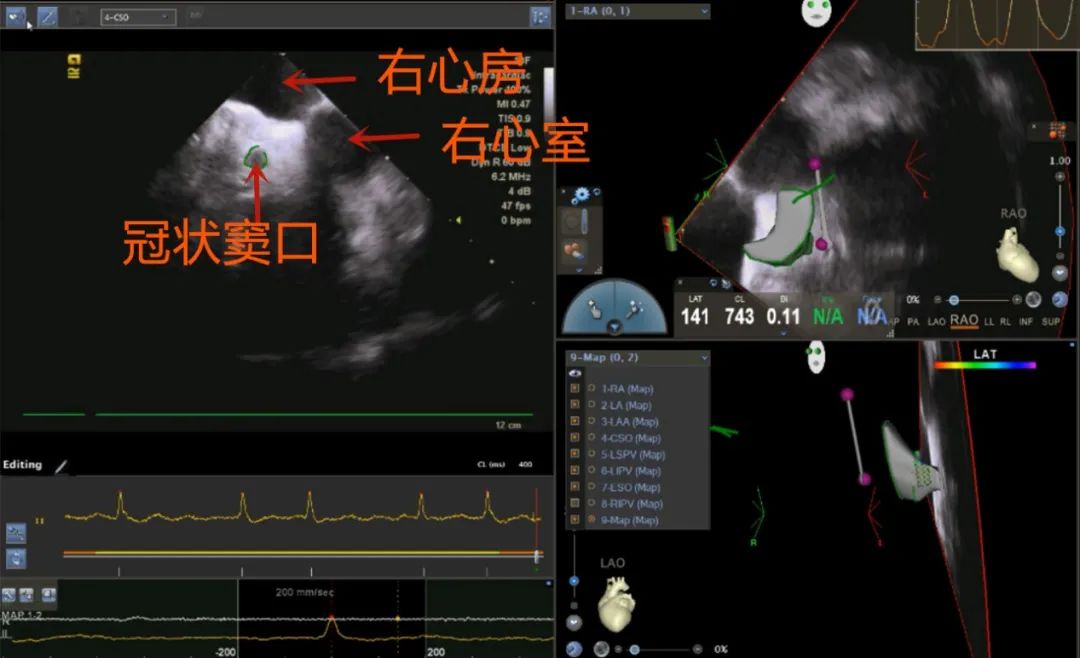

术中,穿刺股静脉,首先由股静脉置入腔内超声导管置右心房,不同操作旋转导管,建立冠状窦、左心房体部、左右侧上下肺静脉、左心耳、食道等重要解剖结构。随后,穿刺锁骨下静脉,置入冠状窦电极,经股静脉置入导引导丝,沿导丝送入穿刺鞘、穿刺针,进行房间隔穿刺。通过超声检测心包下,进行射频消融术隔离肺静脉,完成肺静脉隔离,证实房颤起源于肺静脉,消融隔离后患者房颤反复诱发不再发作,手术成功。术后患者恢复良好,观察两天康复出院。

超声扫描重建冠状窦口